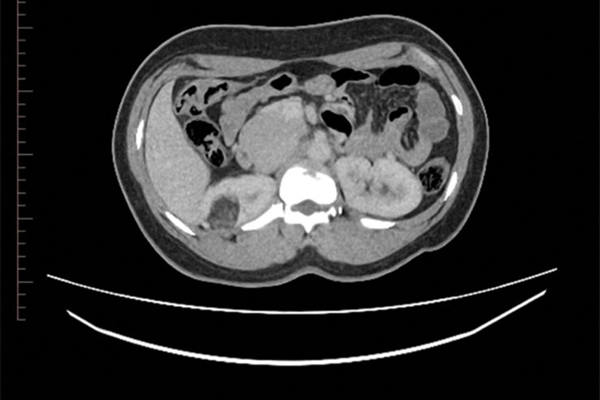

Upper tract abnormalities

The role of embolisation in urology

Benign upper tract abnormalities